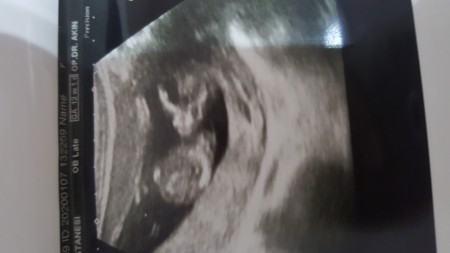

Kızlar önce kız dedi direk daha sonra bi çıkıntı gibi bse gördü ama emin olamadı plesentada olabilir dedi %50 kız %50 erkek dedi kafa karıştı bizim :):angry::D

Nub teorisine göre erkek bu arada ben oranı yüzde 75 e çekiyorum :)))

Canm burda bize sinirli bakan bi bebek var bence tahmin etmesek daha iyi olur :D doktor ikiside olabikir demiş kisacasi söylememiş :D kac haftalik

Çıkıntı görür  gibi olunca ondan öyle dedi sanırım doktorda bse diyemedi plesentada olabilir dedi bizi arada bıraktı:))

Maşallah canım kıza benziyor sağlıkla kucağına al(;

Kız bence canım

Erkek geldi icimden  :)

Erkek bencede